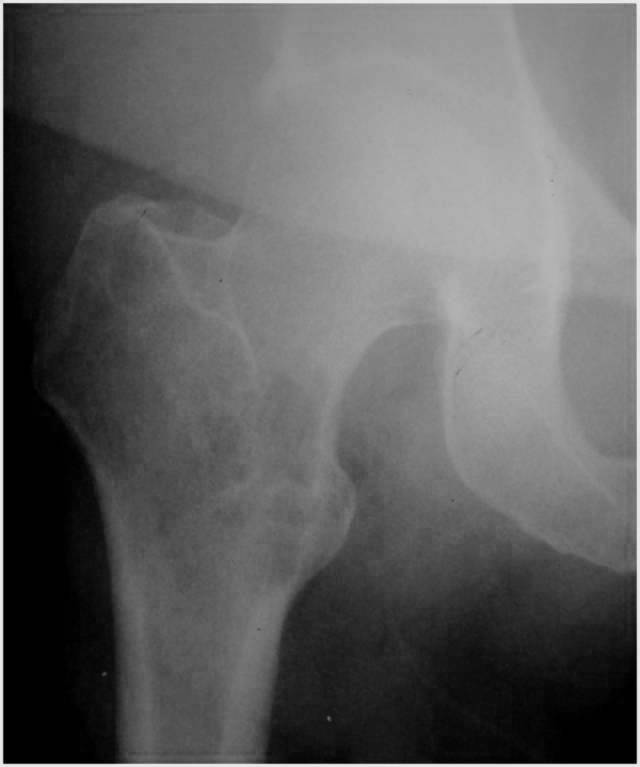

Describe this XRay? 15yo boy with painful mass. Differential? Top Diagnosis? Prognosis and Prognostic factors?

EWING SARCOMA